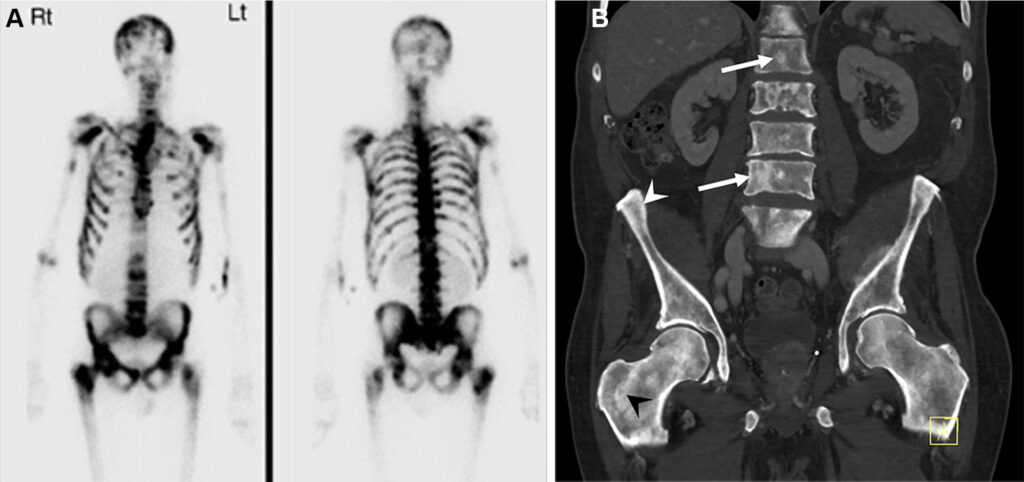

Superscan in un uomo di 68 anni con cancro alla prostata.

(A) Le scintigrafie ossee whole-body in proiezione anteriore e posteriore con 99mTc-MDP mostrano una captazione diffusa nello scheletro assile e appendicolare prossimale, con una captazione nei tessuti molli e renale significativamente ridotta rispetto all’assorbimento scheletrico, compatibile con un aspetto in “superscan” secondario a diffuse metastasi osteoblastiche. (B) L’immagine TC dell’addome con ricostruzione coronale mostra diffuse metastasi ossee sclerotiche che coinvolgono il rachide lombare, il bacino e i femori prossimali. La malattia metastatica può manifestarsi in modo variabile, spaziando da lesioni blastiche a litiche e da lesioni solitarie a multifocali.